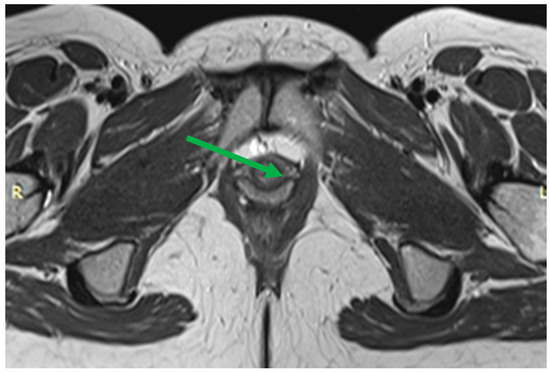

Ligaments appear as symmetrically arranged thin linear structures of low signal intensity on T2-WI. The pelvic floor muscles also have a uniform low signal intensity on T2-WI but are thicker. The signs of partial damage include asymmetric thinning, structure separation, tortuosity of fibers course, and an irregular increase in their signal intensity on T2-WI (Figure 5). A sign of complete damage may be the disruption of the integrity of a muscle or ligament fiber course and/or its fragmentation into several parts. Normally, the iliococcygeal muscle can have a different thickness depending on the state of rest or tension, which is 2.9–3.9 mm [37]. The puborectal muscle is usually 4.9–6.5 mm in size.

Normal urethra looks like a “target” on axial T2-WI. The mucosal and submucosal layers are characterized by high signal intensity, the transverse striated muscle layer is hypointense, and the middle smooth muscle layer is hyperintense (Figure 7). Shortening of the urethra and insufficiency of its sphincter can be assessed by dMRI. Patients usually have stress urinary incontinence similar to that of UH. When the urethra is less than 3 cm in length, it can be seen to be shortened on MRI scans [50].

Figure 7. Normal urethra (arrow) on axial T2-WI: The mucosal and submucosal layers have high signal intensity, the transverse striated muscle layer is hypointense, and the middle smooth muscle layer is hyperintense. Thinning of the transverse striated urethral sphincter muscle is also associated with urinary loss [51], although the relationship is debated [52,53]. Weakening of the urethral sphincter can lead to urethral diverticulum formation (Figure 8). These changes can manifest as urethral obstruction, followed by infection of the paraurethral glands. Diverticula can vary in size, with the larger ones looking like a fluid-filled pouch surrounding the urethra. To make this diagnosis, it is sufficient to perform a normal MRI examination without performing functional tests with pressure.